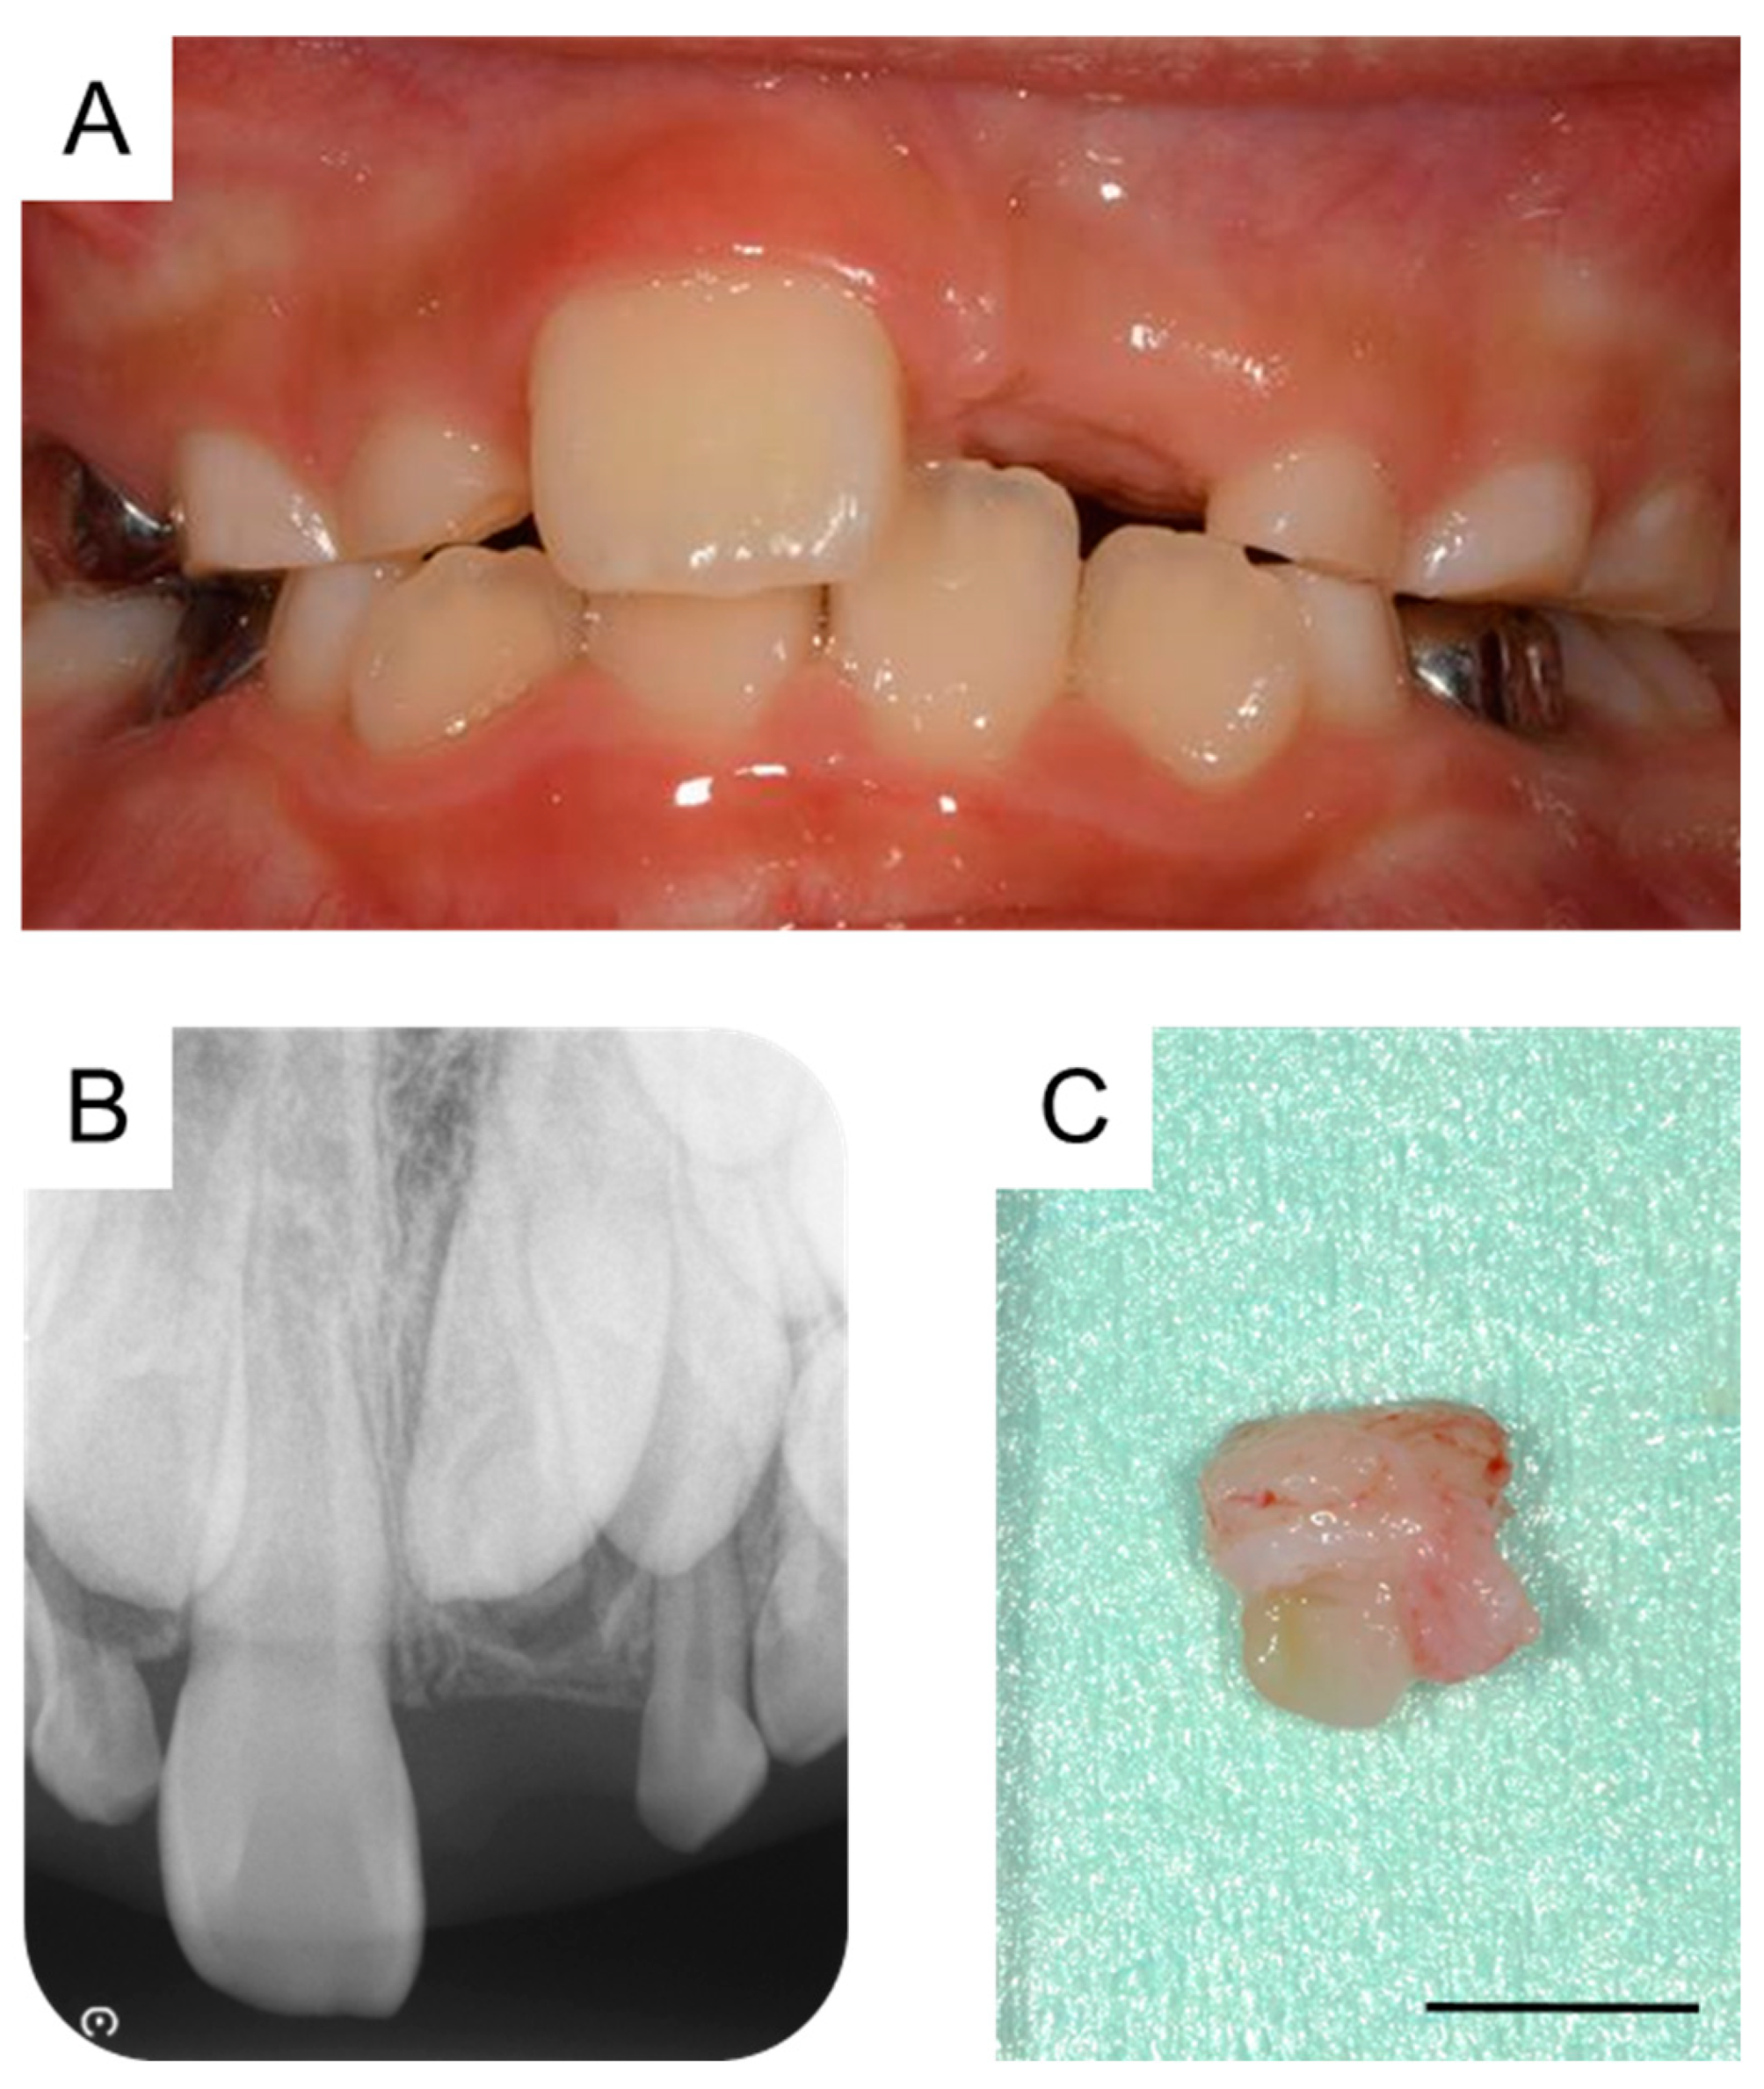

By the time the patient was aged 8 years and 2 months, the permanent maxillary left central incisor had not erupted in the oral cavity (Figure 3A). A periapical radiograph revealed the presence of a calcified tissue near the crown of the permanent maxillary left central incisor (Figure 3B). Considering the difference in the eruption time of the bilateral permanent maxillary central incisors, we decided to take an immediate surgical approach. One month later, we surgically removed the calcified tissue and the bone covering the permanent maxillary left central incisor under physical restraint. The extracted calcified tissue measured 5 mm × 5 mm (Figure 3C). Histopathological examination showed the presence of a tooth-like structure with enamel, dentin, pulp, and reduced enamel epithelium, confirming the diagnosis of a third supernumerary tooth (Figure 4).

Figure 3. Extraction of the third supernumerary tooth. (A) Intraoral photograph at the age of 8 years and 2 months. (B) Periapical radiograph showing the third supernumerary tooth at the age of 8 years and 2 months. (C) Extracted calcified tissue, which was later diagnosed as the third supernumerary tooth. Scale bar: 5 mm.